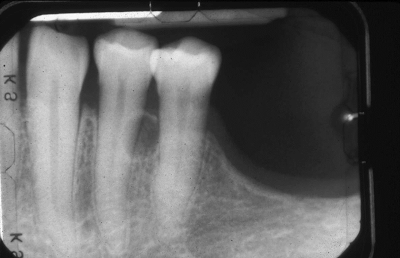

Lateral Periodontal Cyst

Developmental odontogenic cyst – typically occurs aong the LATERAL ROOT SURFACE inside bone

Arise from rests of dental lamina – RESTS of SERRES

Premolar-Canine-Lateral Incisor region

TEETH ARE VITAL

Unilocular or Multilocular (botryoid odontogenic cyst)

Recurrence is RARE